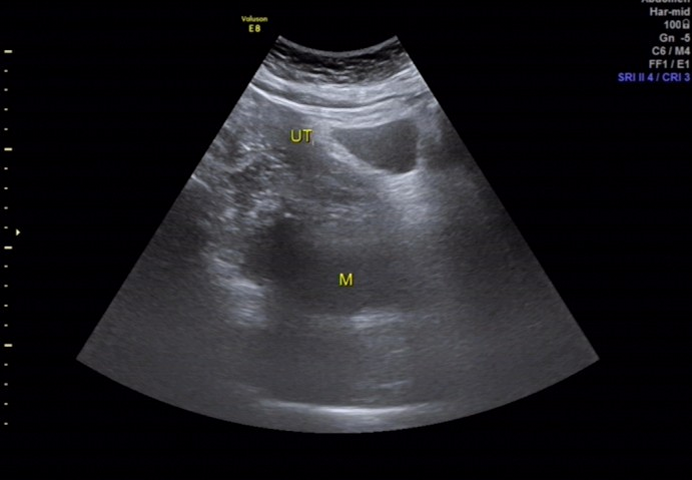

超声所见

骶尾部皮下软组织层内探及一范围约 145×98×107mm 的低回声包块,围绕骶骨生长,部分向盆腔内生长,与周围其他组织分界清楚,内部回声欠均匀, CDFI:内见多个条状血流信号, PW 检测:呈动脉频谱, RI:0.72 。

图 8 用凸阵探头经下腹部扫查可见包块部分向盆腔生长